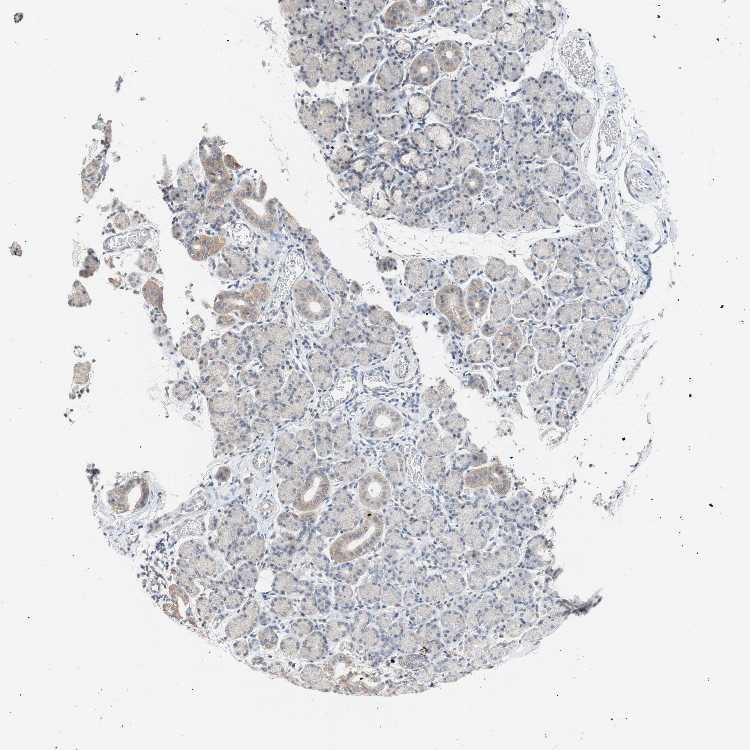

SALIVARY GLAND - Antibody stainingi

Antibody staining in the annotated cell types in the current human tissue is reported as not detected, low, medium, or high, based on conventional immunohistochemistry profiling in selected tissues. This score is based on the combination of the staining intensity and fraction of stained cells.

Each image is clickable and will lead to virtual microscopy that enables deeper exploration of all samples and also displays staining intensity scores, fraction scores and subcellular localization as well as patient and tissue information for each sample.

Antibody HPA014193Antibody CAB009517

Glandular cells LowNot detected